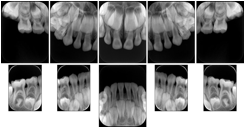

Intra-oral radiography typically involves acquisition of multiple images of various parts of the dentition. Many digital radiographic systems offer customized templates that are used for displaying the images in a study on the screen. These templates may also be referred to as mounts or view sets. The Structured Display Object represents a standard method of encoding and exchanging the layout and intended display of Structured Displays. A structured display object created in this manner could be stored with a study and exchanged with images to allow for complete reproduction of the original exam.

1. A patient visits a General Dentist where a Full Mouth Series Exam with 18 images is acquired. The dentist observes severe bone loss and refers the patient to a Periodontist. The 18 images from the Full Mouth Series along with a Structured Display are copied to a DICOM Interchange CD and sent with the patient to see the specialist. The Periodontist uses the CD to open the exam in his Dental Radiographic Software and consults via phone with the General Dentist. Both are able to observe the same exam showing the images on each user's display using the exact same layout.

Intra-oral Full Mouth Series Structured Display

Figure OO-1. Intra-oral Full Mouth Series Structured Display